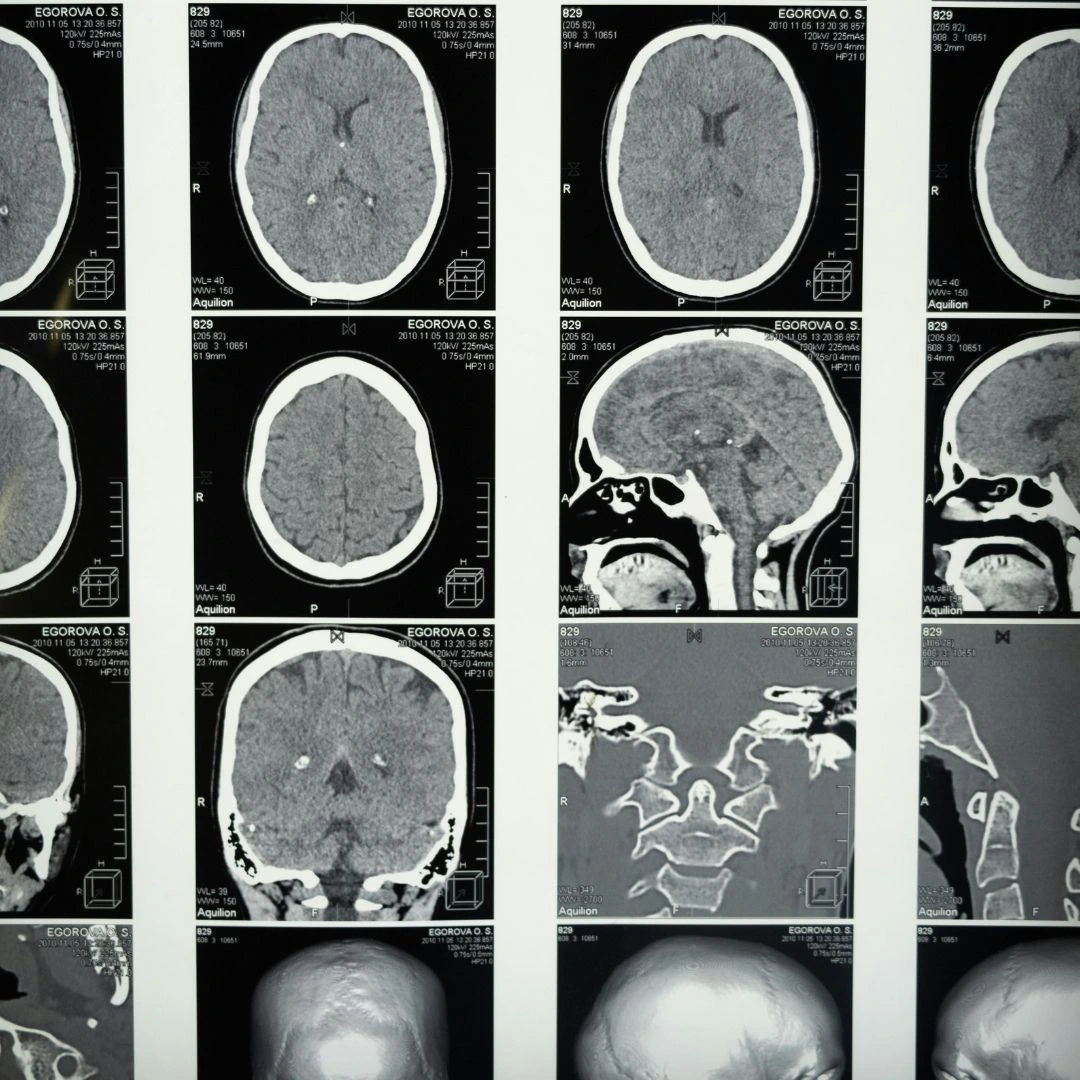

The idea that the brain drastically changes isn’t unfounded. According to Mariam Arain et al., the frontal lobe—the part of the brain responsible for a wide range of essential functions, including movement, cognition, and emotional regulation—doesn’t fully mature until around the age of 25. This late maturation is due to the brain’s “back-to-front” pattern of development, which means the prefrontal cortex is one of the last regions to fully develop.

What does that mean? Simply put, as the frontal lobe finishes developing, your brain’s “executive skills,” like judgment and decision-making, problem-solving, reasoning, impulse control, and planning, become more solid. The result? Fewer purely “gut-feel” choices, and more decisions guided by logic and reflection. A departure from the emotional volatility that most people experience in their teens and early 20s.

Banner photos by Cotton Bro Studios via Pexels.